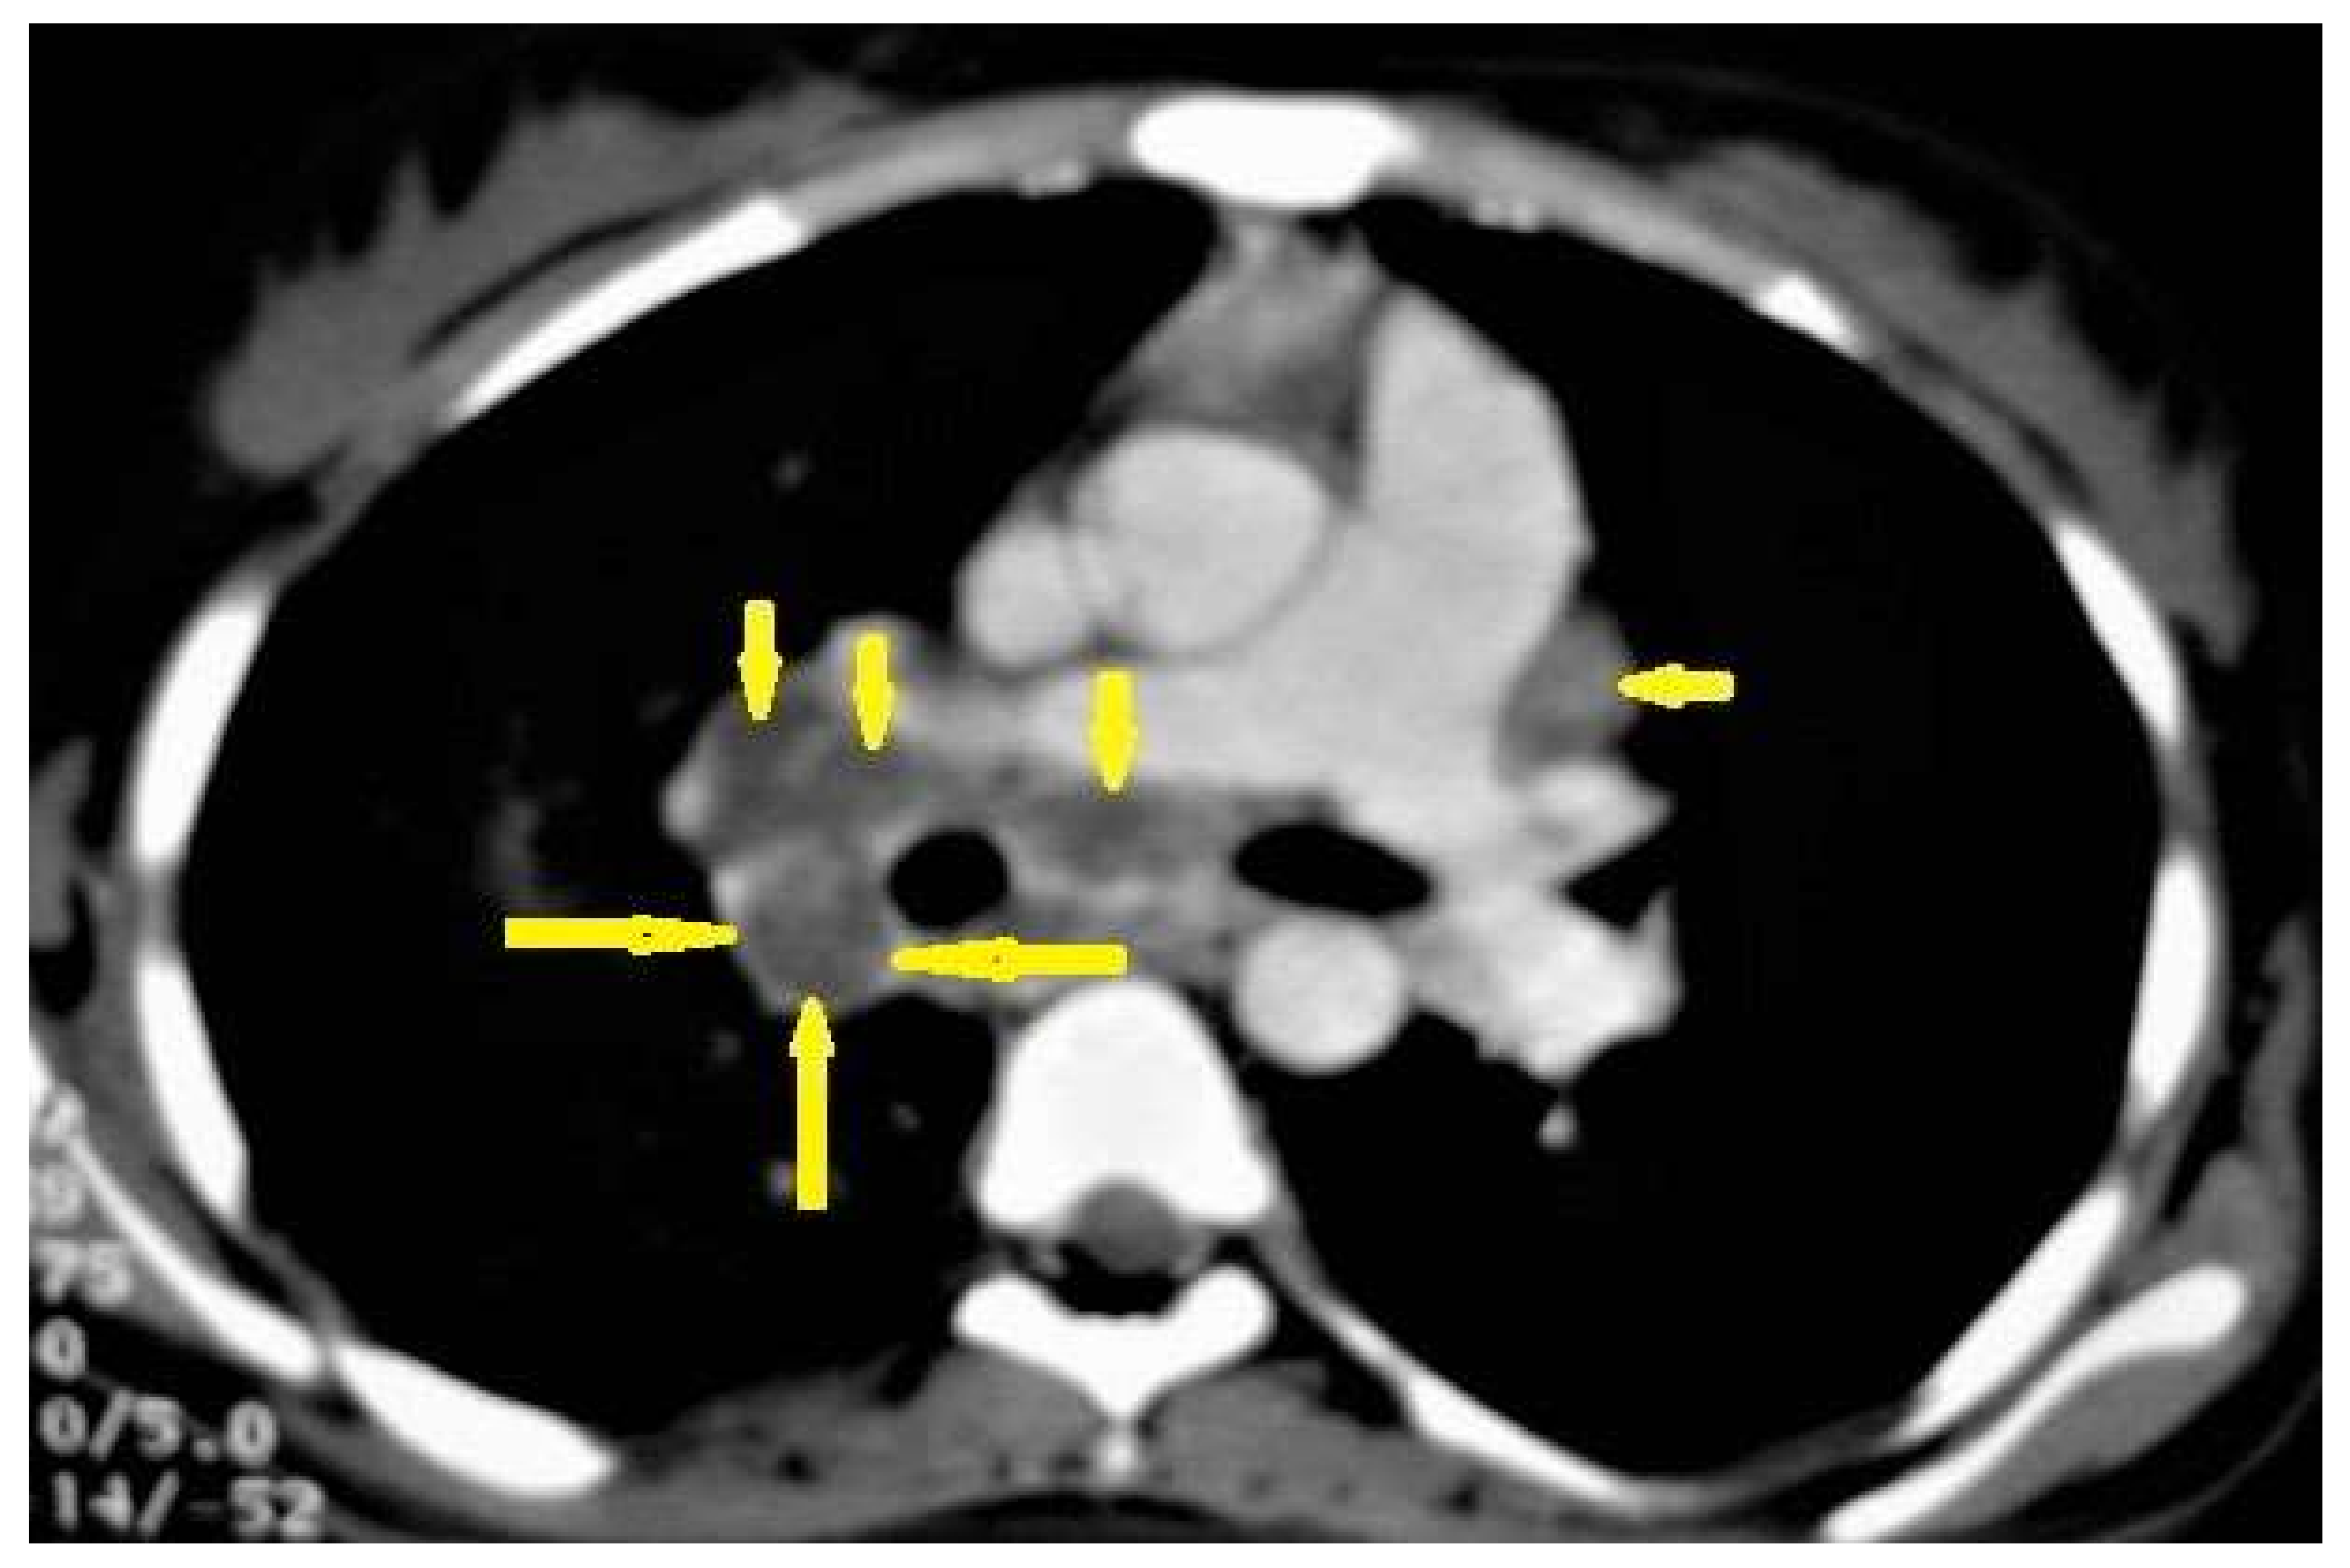

2.3. Cardiovascular System (CVS) TB

The CVS is one of the most common sites (after the CNS) of the extrapulmonary TB, which is an affected system with an unfavorable prognosis. It affects the heart through lymphatic spread, which comes directly from the lungs or the pleura or hematogenous spread in miliary TB. TB can affect the pericardium, the myocardium, and the aorta. Pericardial involvement is relatively common, especially in patients with acquired immunodeficiency syndrome (AIDS). However, tuberculous myocarditis and aortitis are relatively rare manifestations. Transthoracic echocardiography (TTE) and cardiac MRI are imaging methods for the evaluation of the heart and pericarditis. CT allows the evaluation of the aorta for aortitis and the localization of aneurysms [36].

Pericardial involvement in TB can occur as pericardial effusion, constrictive pericarditis, or both. In developing countries, more than half of large pericardial effusions are tuberculous in origin, and TB is the most common cause of constrictive pericarditis. TTE is the initial imaging method to detect suspected pericardial effusion. CTs and MRIs are useful in detecting lobulated effusions and pericardial thickening. CTs have the advantage of detecting pericardial calcifications, which are a frequently found in constrictive pericarditis [37,38].

• Pericardial effusion (Figure 8b) occurs in 85% of tuberculous patients with AIDS [36]. This may be associated with pericardial thickening and determining the cause of effusion by imaging is difficult [38]. Pericardial effusion has a wide range of differential diagnosis, including malignancy, infection, uremic, iatrogenic, idiopathic, heart failure, and autoimmune [39].

Figure 1. Primary TB in an 18-year-old man. Axial mediastinal-window CT image shows multiple enlarged mediastinal lymph nodes (short arrows), and right hilar lymph nodes are characterized by central low density and peripheral enhancement after contrast administration forming the rim sign (long arrows).